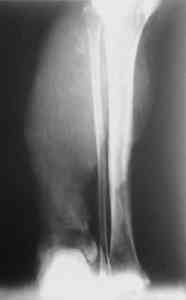

После совместного осмотра с зав.отд.микрохирургии пациент госпитализирован в клинику микрохирургии. Дежурными врачами этой же клиники принято решение сохранить конечность, выполнены ПХО, фиксация спицами, гипсовая иммобилизация. Результаты - см.приложение.